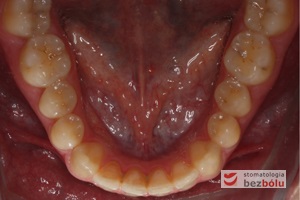

Młody 28-letni, pogodny, stale uśmiechnięty pacjent zgłosił się celem korekcji wad zębowych ograniczających pełną ekspresję uśmiechu. Głównym problemem był dodatkowy siekacz boczny (dwójka) po stronie prawej w łuku górnym. Dodatkowy ząb spowodował stłoczenia pozostałych zębów w łuku górnym oraz przesunięcie linii pośrodkowej. Obliczenia dostępnego miejsca dla siekacza bocznego wpłynęły na wybór zęba przeznaczonego do ekstrakcji. Usunięto dwójkę ustawioną dowargowo, zaś jej „siostrę bliźniaczkę” skierowaną w stronę podniebienia wprowadzono do łuku zębowego w drodze leczenia ortodontycznego. Problemem było szczelne zamknięcie szpary poekstrakcyjnej z powodu nadmiaru miejsca w kości. Wyrównano linię pośrodkową. Leczenie przeprowadzono jednym łukiem ortodontycznym górnym, dolny łuk zębowy nie wymagał założenia aparatu. Po zdjęciu zamków korekcję detali przeprowadzono z użyciem pozycjonera wykonanego w technice termoformingu. Stabilizację efektów leczenia zapewnił stały retainer klejony do powierzchni podniebiennych siekaczy górnych.